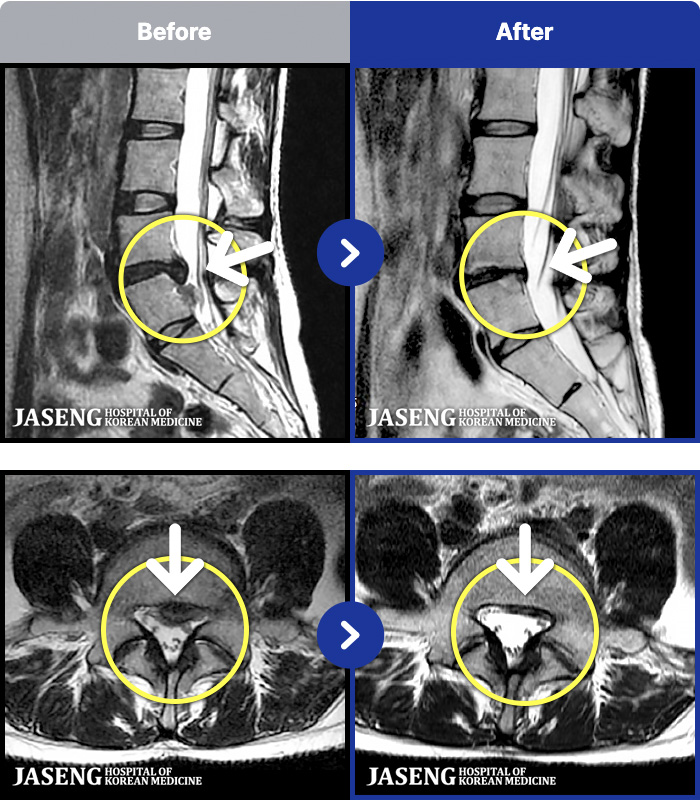

MRI ġ

1,301 MRI ũ ʸ Ȯϼ.

Ƹ ϰ ־.